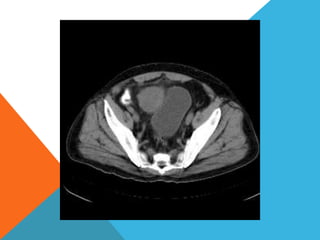

El paciente presentó síntomas de sangrado digestivo y pérdida de peso. Exámenes revelaron gastritis crónica asociada a H. pylori. Un tumor fue descubierto en una colonoscopia normal. La cirugía removió un tumor fibroide solitario, una rara neoplasia mesenquimal que usualmente crece lento y tiene bajo potencial de malignidad. El pronóstico después de la remoción quirúrgica es generalmente bueno.